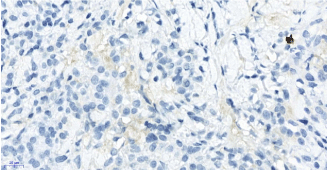

Figure 2a. Neoplasm consisted of monotonous plasma cells with middle-sized cytoplasm and eccentric nucleus. HE X400